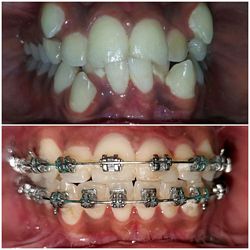

Case No: 15

Malocclusion Type: Skeletal Class II Malocclusion with Overjet of 10mm and Overbite of 7mm Mechanics: MBT Appliance (3M Metal Brackets)(Note: No Functional Appliance Used)

Intra-oral : Pre-treatment : Frontal View

Intra-oral : Post-treatment : Frontal View

Intra-oral : Pre & Post treatment : Frontal View : 10 mm Overjet Reduced